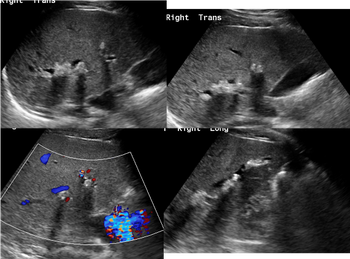

A 23-year-old male with alcohol consumption with elevated liver enzymes. Ultrasound shows intrahepatic ductal dilatation involving Seg 6 RLL with muliple echogenicity with posterior shadowing represent calculi.